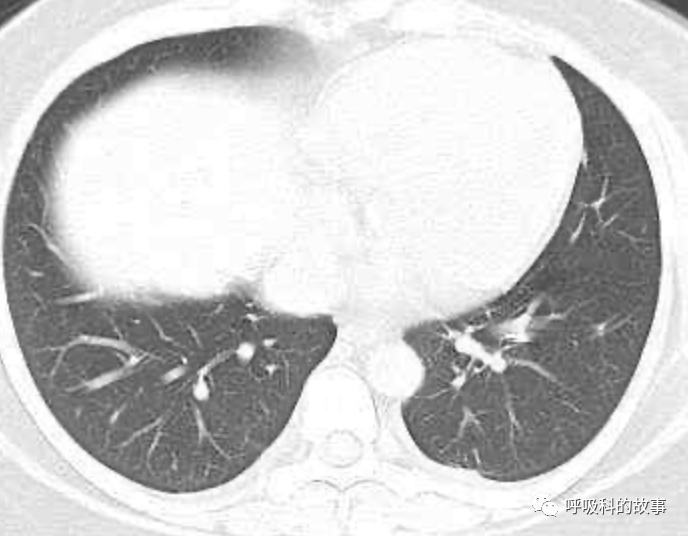

患者发热后行胸部CT检查(6月21日,住院第13天),可见两下肺有条片影,当时考虑是肺炎引起的发热。

可是在6月26日(往院第18天)仍持续发热的情况下复查肺部CT,肺部病灶已明显吸收了。那么患者发热的原因到底是什么呢?为什么患者高热的情况下血白细胞不升反降,C反应蛋白也没有明显增高?这个时候消化科医生也迷茫了,这可怎么办?于是请感染科和呼吸科医生一起会诊,共商计策。